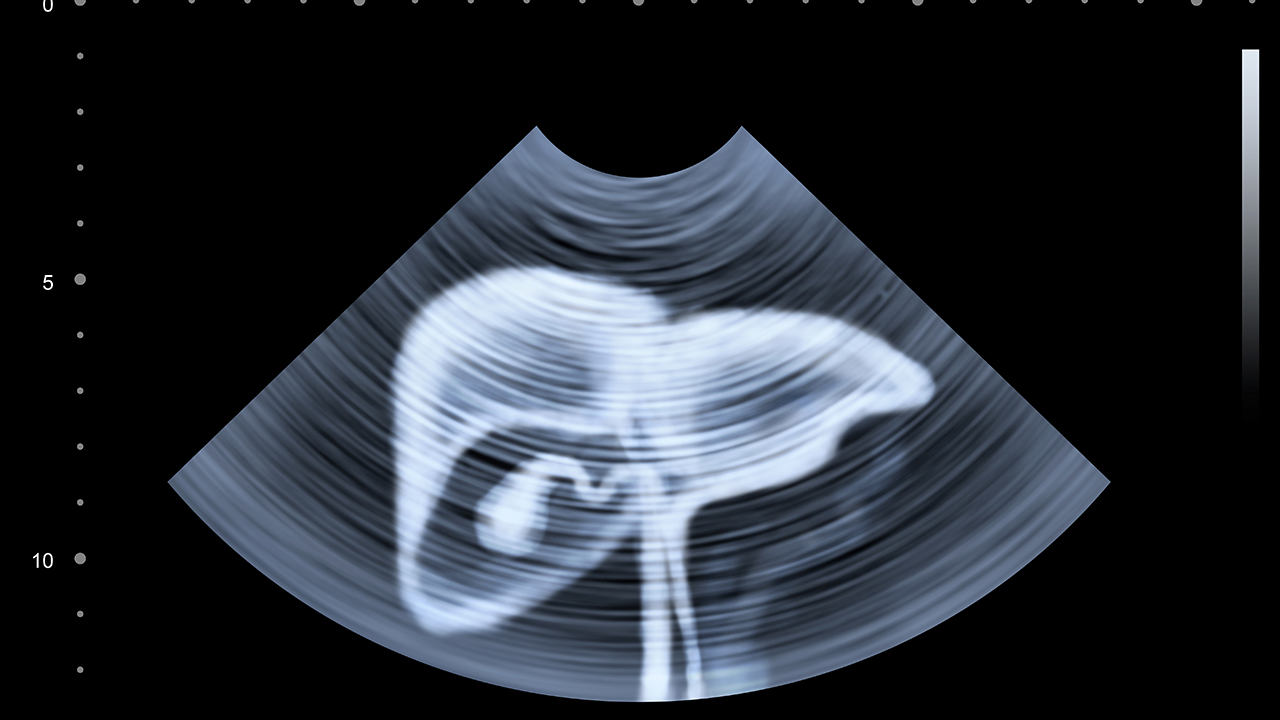

广州市第一人民医院肝胆外科是广东省重点专科,在肝癌综合治疗方面经验丰富。医院开展肝癌的规范化诊疗,建立了完善的随访体系。同时,医院还注重肝癌的早期筛查,通过超声、CT等检查手段提高早期诊断率,为患者争取佳治疗时机。

肝癌的预防与健康管理至关重要。对于高危人群,如慢性乙肝、丙肝患者、肝硬化患者等,应定期进行肝脏超声和甲胎蛋白检查,实现早发现、早治疗。日常生活中要避免酗酒、发霉食物等危险因素,保持良好的生活习惯。对于已经确诊的患者,要积极配合治疗,定期复查,保持良好的心态。同时,要注意营养支持,保证充足的蛋白质摄入,避免过度劳累,适当进行体育锻炼,提高机体免疫力。